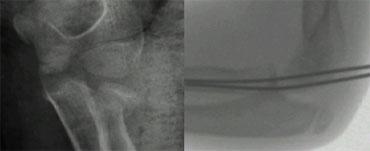

Nếu không có di lệch, việc chẩn đoán có thể gặp khó khăn (hình).

Radial neck fracture with tilt. Notice trochlear ossifications projecting in between humerus and ulna simulating intra-articular fragments.

Nếu độ nghiêng của chỏm quay nhỏ hơn 30° thì bệnh nhân được điều trị bằng đai treo.

Điều quan trọng cần nhận biết là bình thường chỏm quay có một góc nghiêng nhất định (lên đến 15°).

Nếu độ nghiêng lớn hơn 30° thì tiến hành nắn chỉnh kín.

After closed reduction radiograph in cast shows unsuccesfull reduction. K-wire insertion is performed

Khi nắn chỉnh kín không thành công trong việc phục hồi độ nghiêng hoặc khi không thể sấp và ngửa đến 60°, một dây Kirschner được đưa vào để duy trì sự nắn chỉnh.

The radial epiphysis is slipped (arrows). The radiocapitellar line does not pass through the capitellum indicating dislocation and there is a fracture of the olecranon

Gãy cổ xương quay cũng như trật đầu xương quay trong 50% trường hợp có liên quan đến các tổn thương khuỷu tay khác.

Thường gặp nhất là gãy mỏm khuỷu.

Khi đầu xương quay còn rất nhỏ, trượt đầu xương quay có thể bị bỏ sót (hình).